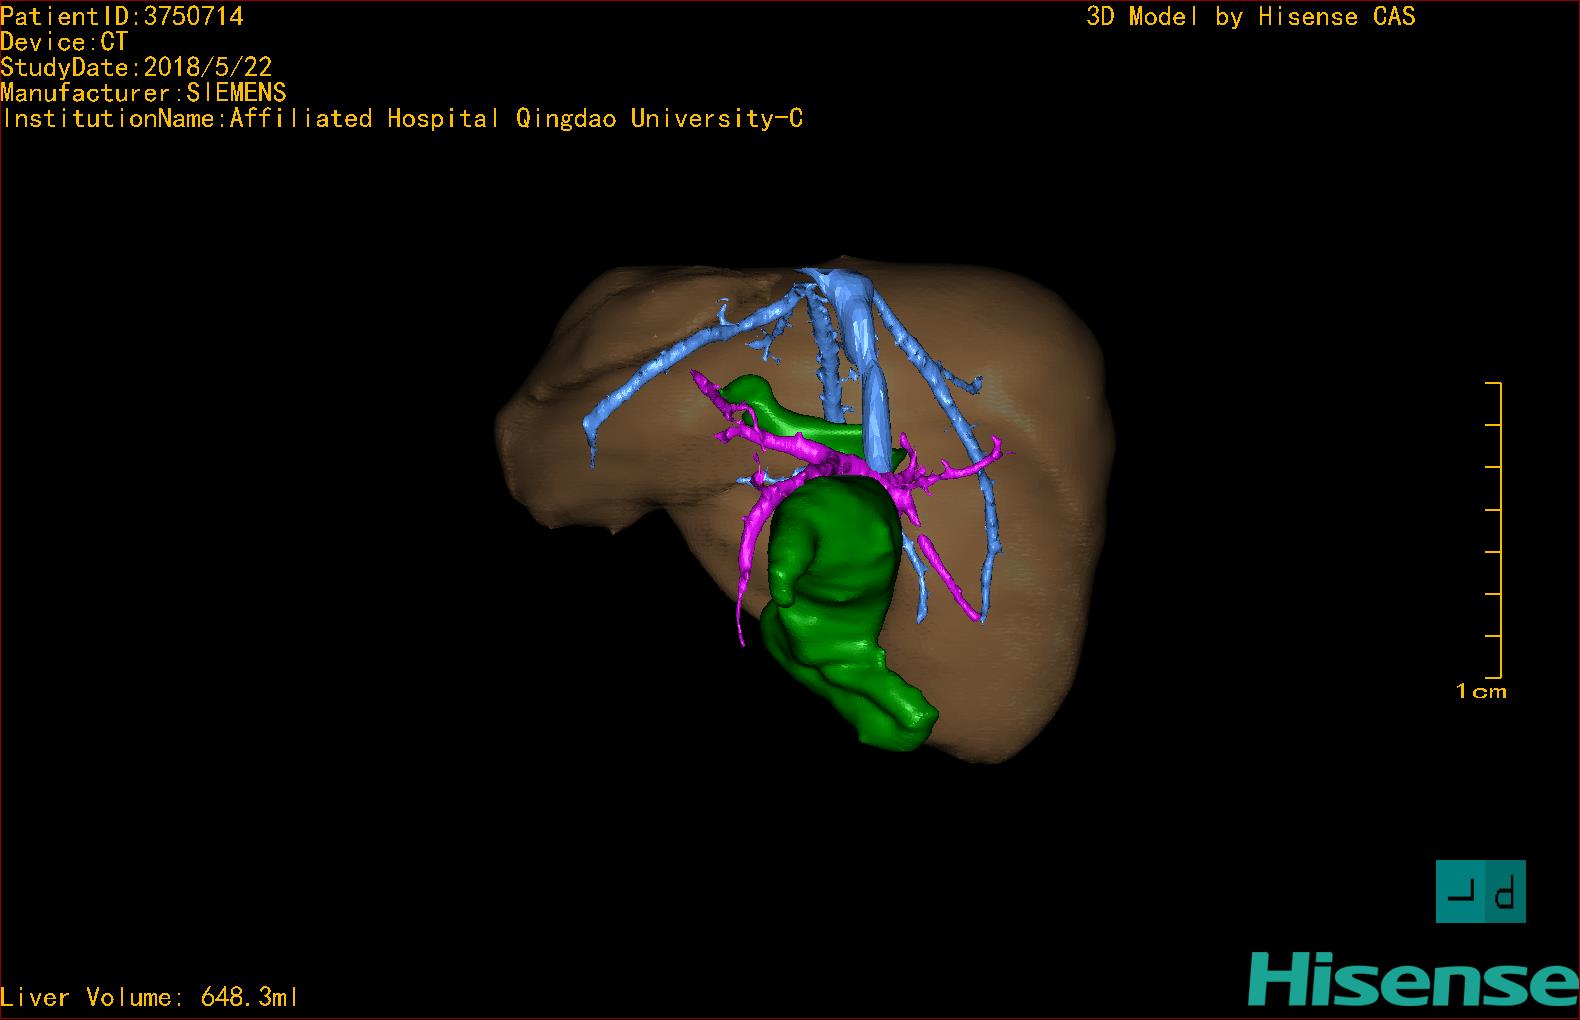

实验室检查: 血常规:WBC 16.16*109/L,NEU2.88*109/L,RBC3.76 1012/L,HB 92g/L, PLT 414*109/L 生化全套:ALT 50.00 U/L, AST 147.00 U/L, ALT/AST 0.34,LDH 367.00 U/L, ALB 36.91g/L, GGT 1297.00 U/L, ALP 1155.00 U/L, BIL-T 138.23 umol/L, BIT-D 97.01 umol/L, TBA 48.40umol/L,ADA 40.00U/L, PAB 121.40mg/L, BUN 1.98 mmol/L, CREA 17.00 umol/L 肝炎全套: 炎症反应标志物:CRP 7.27mg/l 诊疗过程: CT结果输入海信CAS系统后行3D重建及手术规划后,于2018-5-31全麻下行“胆总管囊肿切除+肝总管空肠吻合术”手术治疗: 术前三维重建及手术方案设计: 将0.625mm双源薄层CT资料的静脉期和动脉期Dicom格式文件导入海信CAS系统。 通过调节窗宽窗位调整CT序号,对肝实质,胆囊,下腔静脉,肿瘤,肝动脉、门静脉及肝静脉等进行三维重建;系统自动计算肝脏体积,肝脏体积为648.3ml,通过术前模拟手术,精准判断手术切除范围,进行精密术前规划及讨论后实施手术。 手术步骤: 麻醉成功后,患儿取平卧位,2.5%碘伏消毒手术区皮肤,铺无菌巾单。取右上腹纵口长约5m,切开皮肤、皮下织组,腹直肌前鞘、腹直肌,后鞘和腹膜。探查见:胆总管3×2cm大小,胆囊管迂曲,长约10cm。 剥离、切除胆囊,游离胆总管,将之横断:①近端即肝总管,剪裁后被吻合用;②远端游离切除囊肿内壁,直至胆总管开口于十二指肠处,冲洗后予以结扎缝扎。距treits韧带20cm处横断空肠:①近端与其远端25cm处的空肠侧壁行端侧双层吻合,吻合口通畅;②远端断端封闭,其侧壁剪开,并经横结肠后提至肝门处,与剪裁的肝总管行端侧双层吻合。缝合修补胆囊床及系膜裂孔,肝门部放置橡胶引流管一根。温盐水冲洗腹腔。检查无活动性出血,清点纱布器械无误,依次缝合腹壁各层。手术顺利,麻醉满意,出血不多,未输血,术后病人先进入麻醉恢复室,苏醒后回病房。手术时术者可开启Hisense CAS系统手势控制功能,对肝脏及胆囊解剖结构进行实时、全方观察、评估,起到术中导航作用。 术后病理: 1. (囊肿壁)囊肿性病变,囊壁部分区域衬覆柱状上皮。 2. 慢性胆囊炎。 3. 送检(肝门)淋巴结查见淋巴结1枚,呈反应性增生。 随访情况: 患儿术后2周恢复良好 术前CT检查:动脉期

术前三维重建:重建图片.jpg)